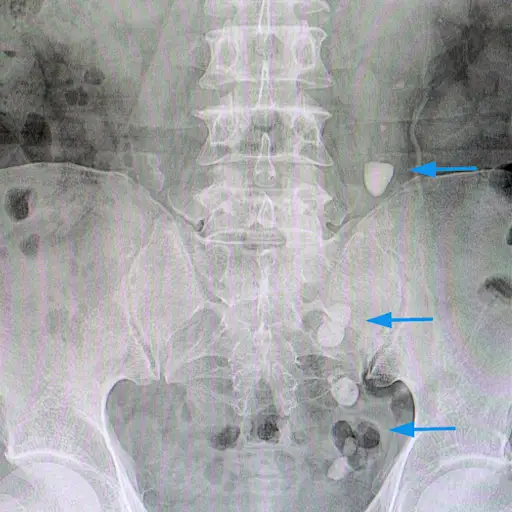

如果您手术删除了小肠的部分,并且您体验了短肠综合征的症状,您的医生可能会检查您,提供血液测试,或检查您的粪便诊断条件。在体检期间,他们会检查维生素缺乏的体重减轻和迹象。血液试验可以显示血液的维生素和矿物质含量。粪便测试可以显示您身体没有吸收多少脂肪和其他营养素。有时,使用X射线或CT扫描。

此外,您的电解质水平可能变得不平衡,导致肌肉问题或不规则的心跳,或者您可能会培养痛苦的肾结石。细菌可能在你的小肠中不受控制地生长(通常占占极少的细菌),导致腹泻或腹胀。